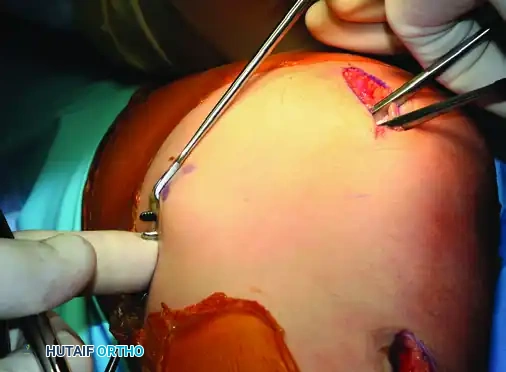

Surgical Technique: Oblique Osteotomy of the Tuberosity

- Lateral Release: Make a 6-cm lateral parapatellar incision, positioned approximately 1 cm lateral to the patellar tendon. Perform a thorough lateral retinacular release extending from the tibial tubercle up to the insertion of the vastus lateralis tendon on the proximal patella. The release is deemed adequate when the patellar articular surface can be manually everted 90 degrees laterally.

- Osteotomy Preparation: Through the same incision, identify the medial and lateral borders of the patellar tendon insertion. Using a 2.5-cm flat osteotome or an oscillating saw, raise a flat osteoperiosteal flap. The bony flap should be approximately 6 cm long and 7 mm thick, tapering anteriorly and remaining hinged distally by the intact distal periosteum. Meticulous care must be taken to avoid violating the posterior soft tissues and neurovascular structures.

- Tubercle Transfer: Rotate the bone flap medially (typically 8 to 10 mm, depending on the preoperative TT-TG calculation), gently cracking the distal cortical hinge.

- Provisional Fixation and Tracking Assessment: Hold the transferred tubercle in its new position with a provisional Kirschner wire. Move the knee through a full passive range of motion while observing patellar tracking (often visualized via a superolateral arthroscopic portal). The patella should engage the trochlea centrally without lateral subluxation or excessive medial tilt.

- Definitive Fixation: Once congruent tracking is confirmed and the tubercle sits flush against the underlying cancellous tibial bed, secure it with one or two AO 4.0-mm or 4.5-mm cancellous lag screws.